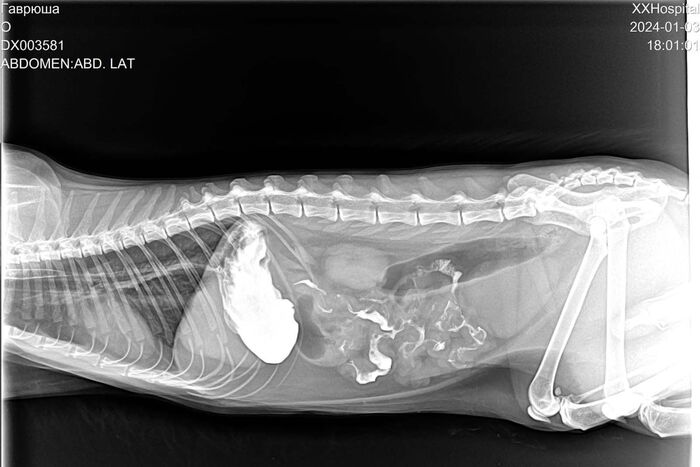

Например, 3 января врачи Донской ветеринарной клиники спасли 6-летнего кота Гаврюшу. На УЗИ в кишечнике обнаружили нечто, похожее на "дождик". Оказалось, что кот проглотил нитку, которая вдобавок запуталась вокруг языка.

Помочь животному можно было только хирургическим путем. Хирург Алексей Демин успешно прооперировал Гаврюшу, сейчас котику ставят капельницы.